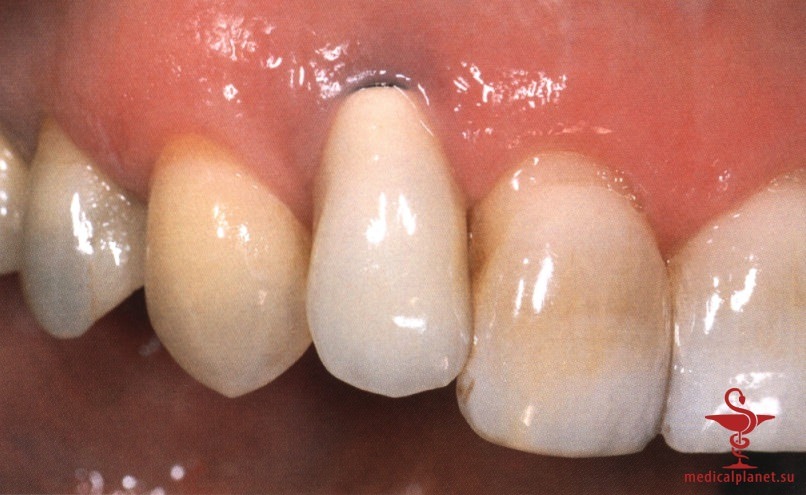

Сложность такого подхода обусловлена высокой вероятностью наличия или формирования костного дефекта в области имплантации. В течение многих лет считалось, что имплантат остеоинтегрируется только при минимальном зазоре между ним и костью. Однако в 1988 г. Carlsson и соавт. описали феномен «костного прыжка», который заключается в возможности достижения остеоинтеграции даже при довольно большом расстоянии между поверхностями имплантата и кости.

Сначала предполагалось, что уменьшение зазора является предпочтительным, поэтому рекомендовали устанавливать имплантаты максимального диаметра. Данное предположение оказалось ошибочным. В настоящее время доказано, что зазор менее 0,5 мм между костью и имплантатом заполняется новообразованной костной тканью без каких-либо дополнительных манипуляций.4 Более того, следует избегать контакта имплантата с костной стенкой, чтобы не оказывать на нее давление, которое сопровождается резорбцией кости (рис. 4).